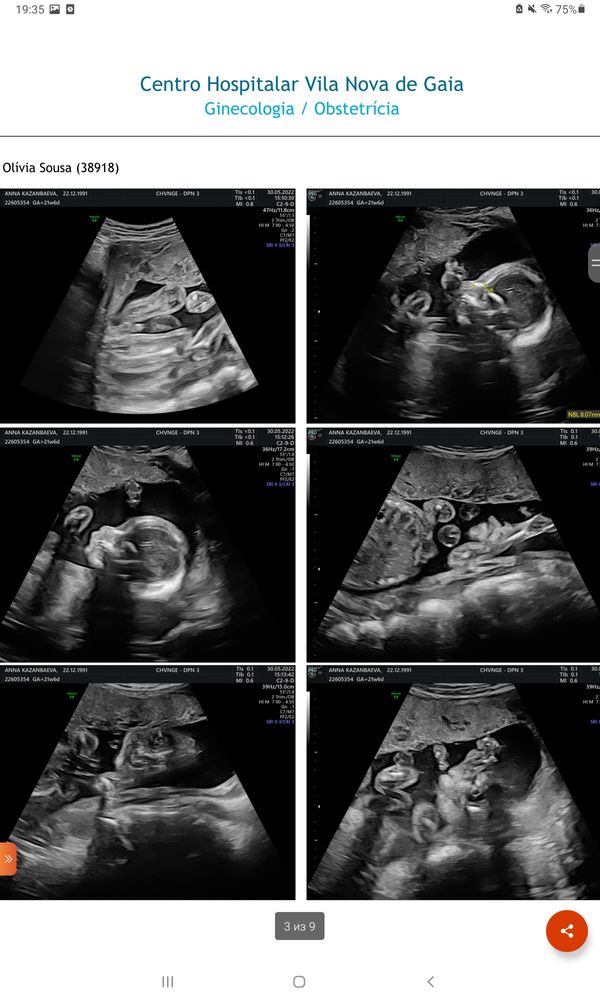

Мальчик или девочка?🙏❤🙂

Изображение На мальчика похоже. Сейчас покажу как у меня, сказали девочка...

Узнать пол по крови Половой бугорок